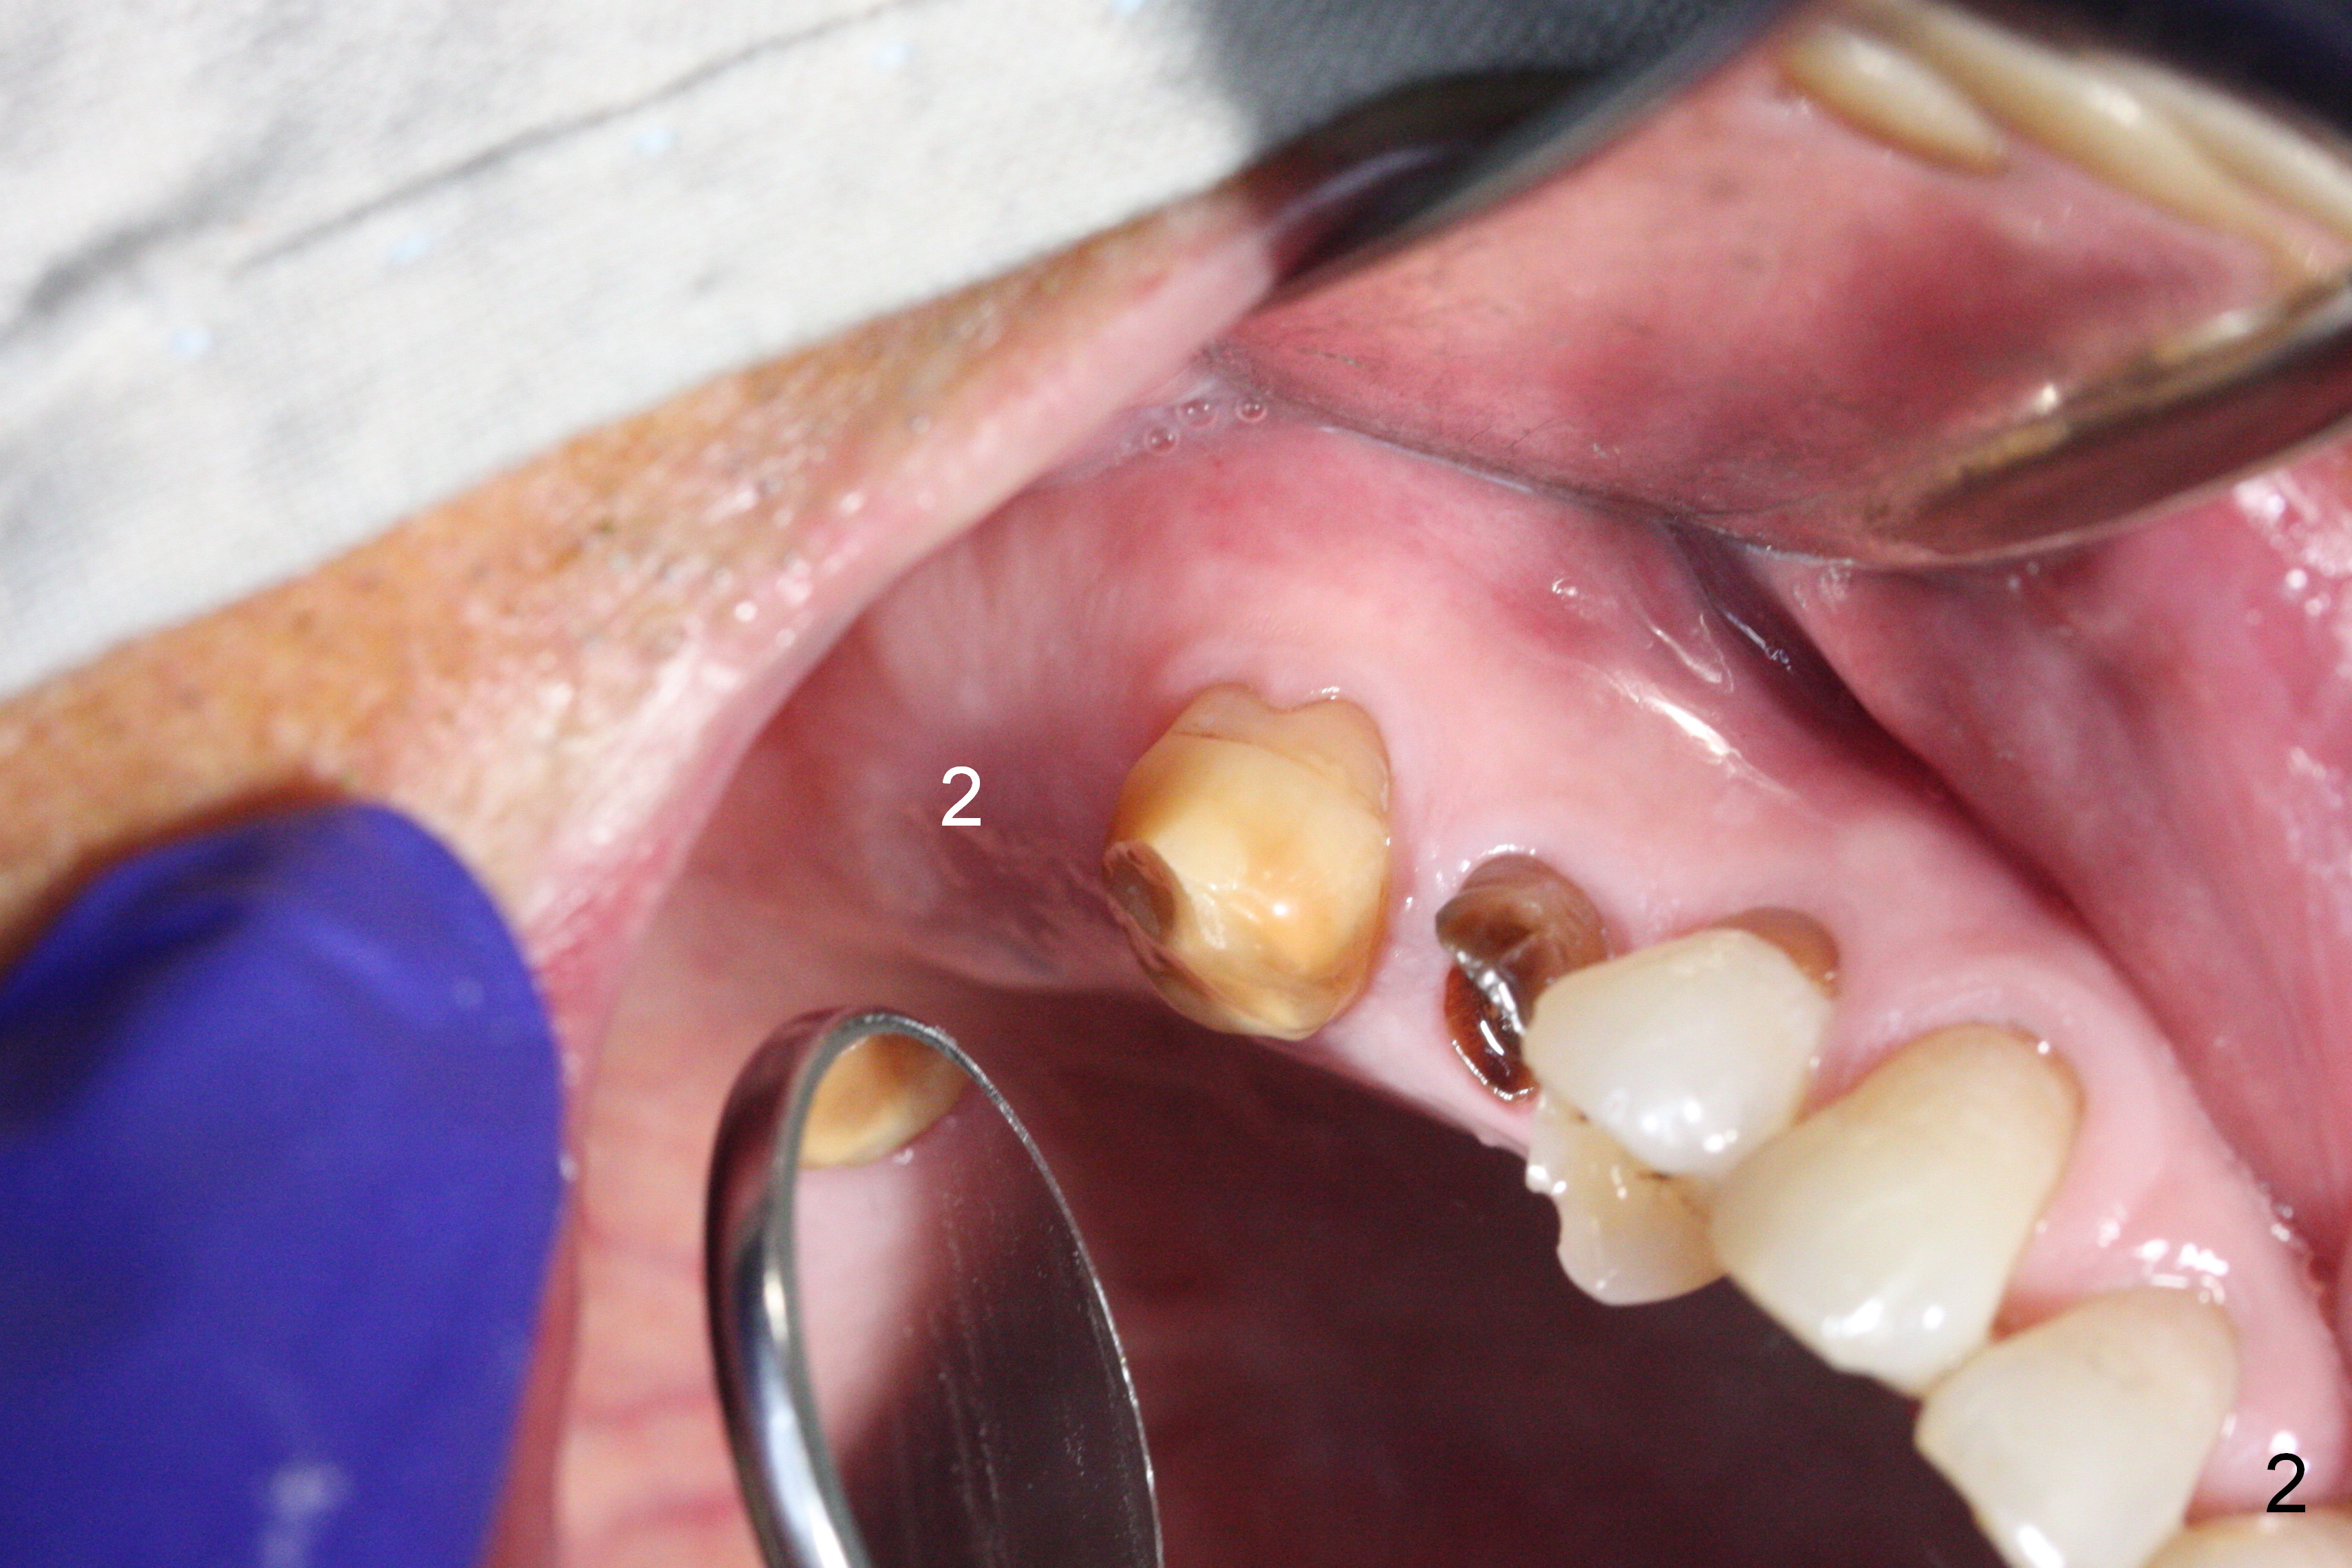

Preop exam shows posterior occlusal collapse (Fig.1) with #3 lost crown and #4 residual root. There is no ridge atrophy at #2 buccopalatally (Fig.2). The root stump of the tooth #4 is oblong, apparently consisting of 2 roots (Fig.3). There is a pointed septum at #4 socket (Fig.4, severe palatal wear of the anterior teeth (^)). After the septum is flattened with surgical handpiece and #8 round bur, 1.6 mm drill is used to start osteotomy in the septum, followed by Magic Drills (MD) and Magic Expanders (ME) alternatively. Osteotomy at #2 is initiated with Magic split, followed by MD and ME in the same manner. Dummy implants are tried in (Fig.5). Because of limited vertical height, Magicore (5.5x9(1) mm) is placed at #2, while a 4x13 mm FC implant 1-2 mm deeper than usual at #4 (Fig.6, ~ 55 Ncm). When a 5x4(2) mm pair abutment is placed at #4, there is no clearance between the Magicore at #2 and the abutment and the opposing dentition. A splinted provisional is fabricated at #3 and 4 to increase the posterior vertical height (Fig.7 P,8). In fact the occlusal contact is confined to the portion of the provisional at #3. The provisional has to extend to #4 to keep bone graft (Fig.6 *) and collagen plug in place. Liquid food is recommended at least 2-3 weeks, since there is no functional occlusal contact on the left. When the wound heals at #4 approximately 2-3 weeks, the splinted provisional can be sectioned with removal the portion at #4 to reduce micro-movement. By the evening the patient is doing well without nasal hemorrhage (sinus lift at #2 (Fig.6 *) or TMJ disturbance (due to increased vertical height).